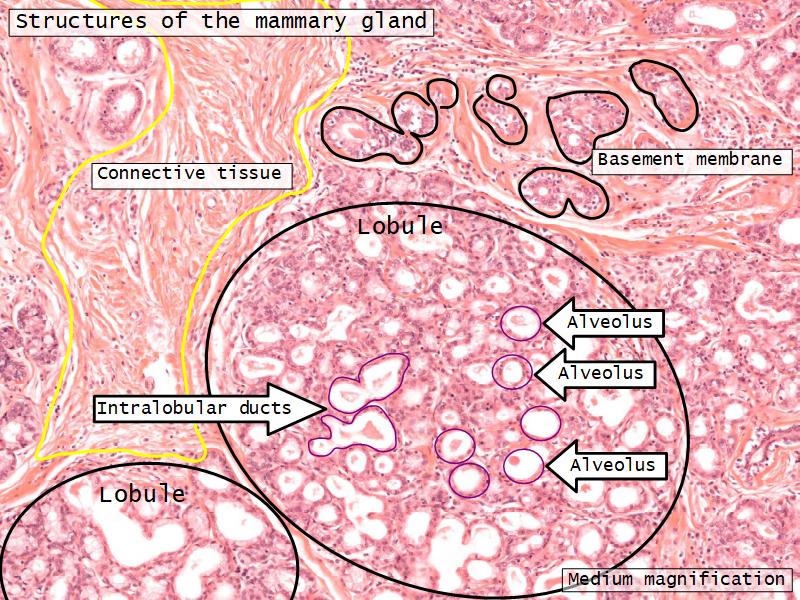

Structures

List the structures and cells found in the mammary gland.

Structures

- Lactiferous sinuses

- Stratified squamous near opening on skin

- Stratified cuboidal other parts

- Lactiferous ducts

- Stratified cuboidal

- Myoepithelial cells

- Underlie lactiferous ducts in most areas

- Basal lamina

- Separate epithelial components from stroma

Active gland

- Much larger than resting phase

- Terminal ducts proliferate to form alveoli

- Alveoli

- Surrounded by incomplete myoepithelial cells